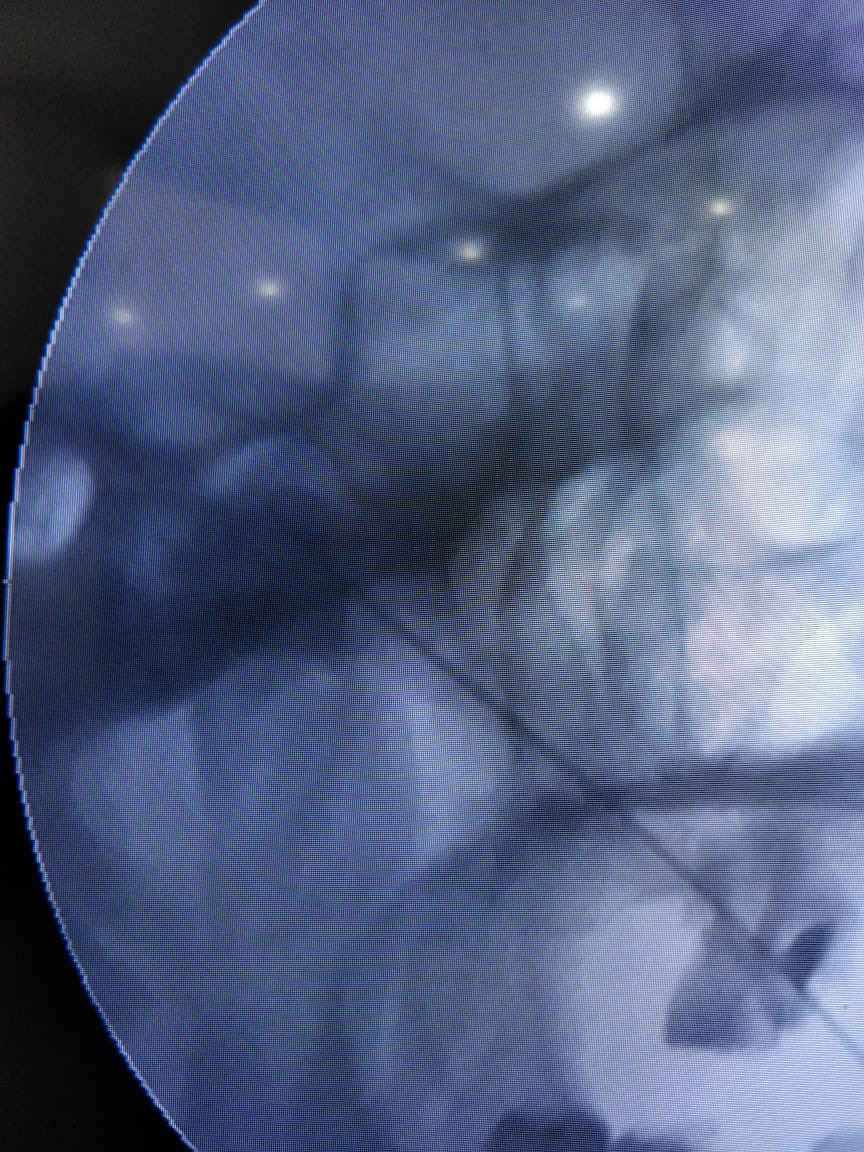

Radiofrequency procedure for #Trigeminal Neuralgia done just now at #Reliefpainservice kashmir. No sedation given. Pulsed RFA for 300 sec, before conventional RFA desensitises the ganglion for heated ablation (RFA). Patient did not require any sedation during the procedure.

tariqtramboo's tweet image. Radiofrequency procedure for #Trigeminal Neuralgia done just now at #Reliefpainservice kashmir.

No sedation given. Pulsed RFA for 300 sec, before conventional RFA desensitises the ganglion for heated ablation (RFA). Patient did not require any sedation during the procedure.